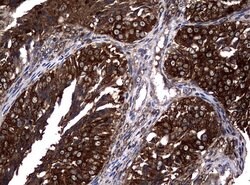

NME1 Mouse anti-Canine, Human, Rat, Clone: UMAB94, liquid, UltraMAB™

NME1 was identified because of its reduced mRNA transcript levels in highly metastatic cells. Nucleoside diphosphate kinase (NDK) exists as a hexamer composed of ′A′ (encoded by this gene) and ′B′ (encoded by NME2) isoforms. Mutations in the gene have been identified in aggressive neuroblastomas. Two transcript variants encoding different isoforms have been found for this gene. Co-transcription of this gene and the neighboring downstream gene (NME2) generates naturally-occurring transcripts (NME1-NME2), which encodes a fusion protein comprised of sequence sharing identity with each individual gene product.Specifications

| Immunocytochemistry, Immunofluorescence, Immunohistochemistry (Paraffin) | |